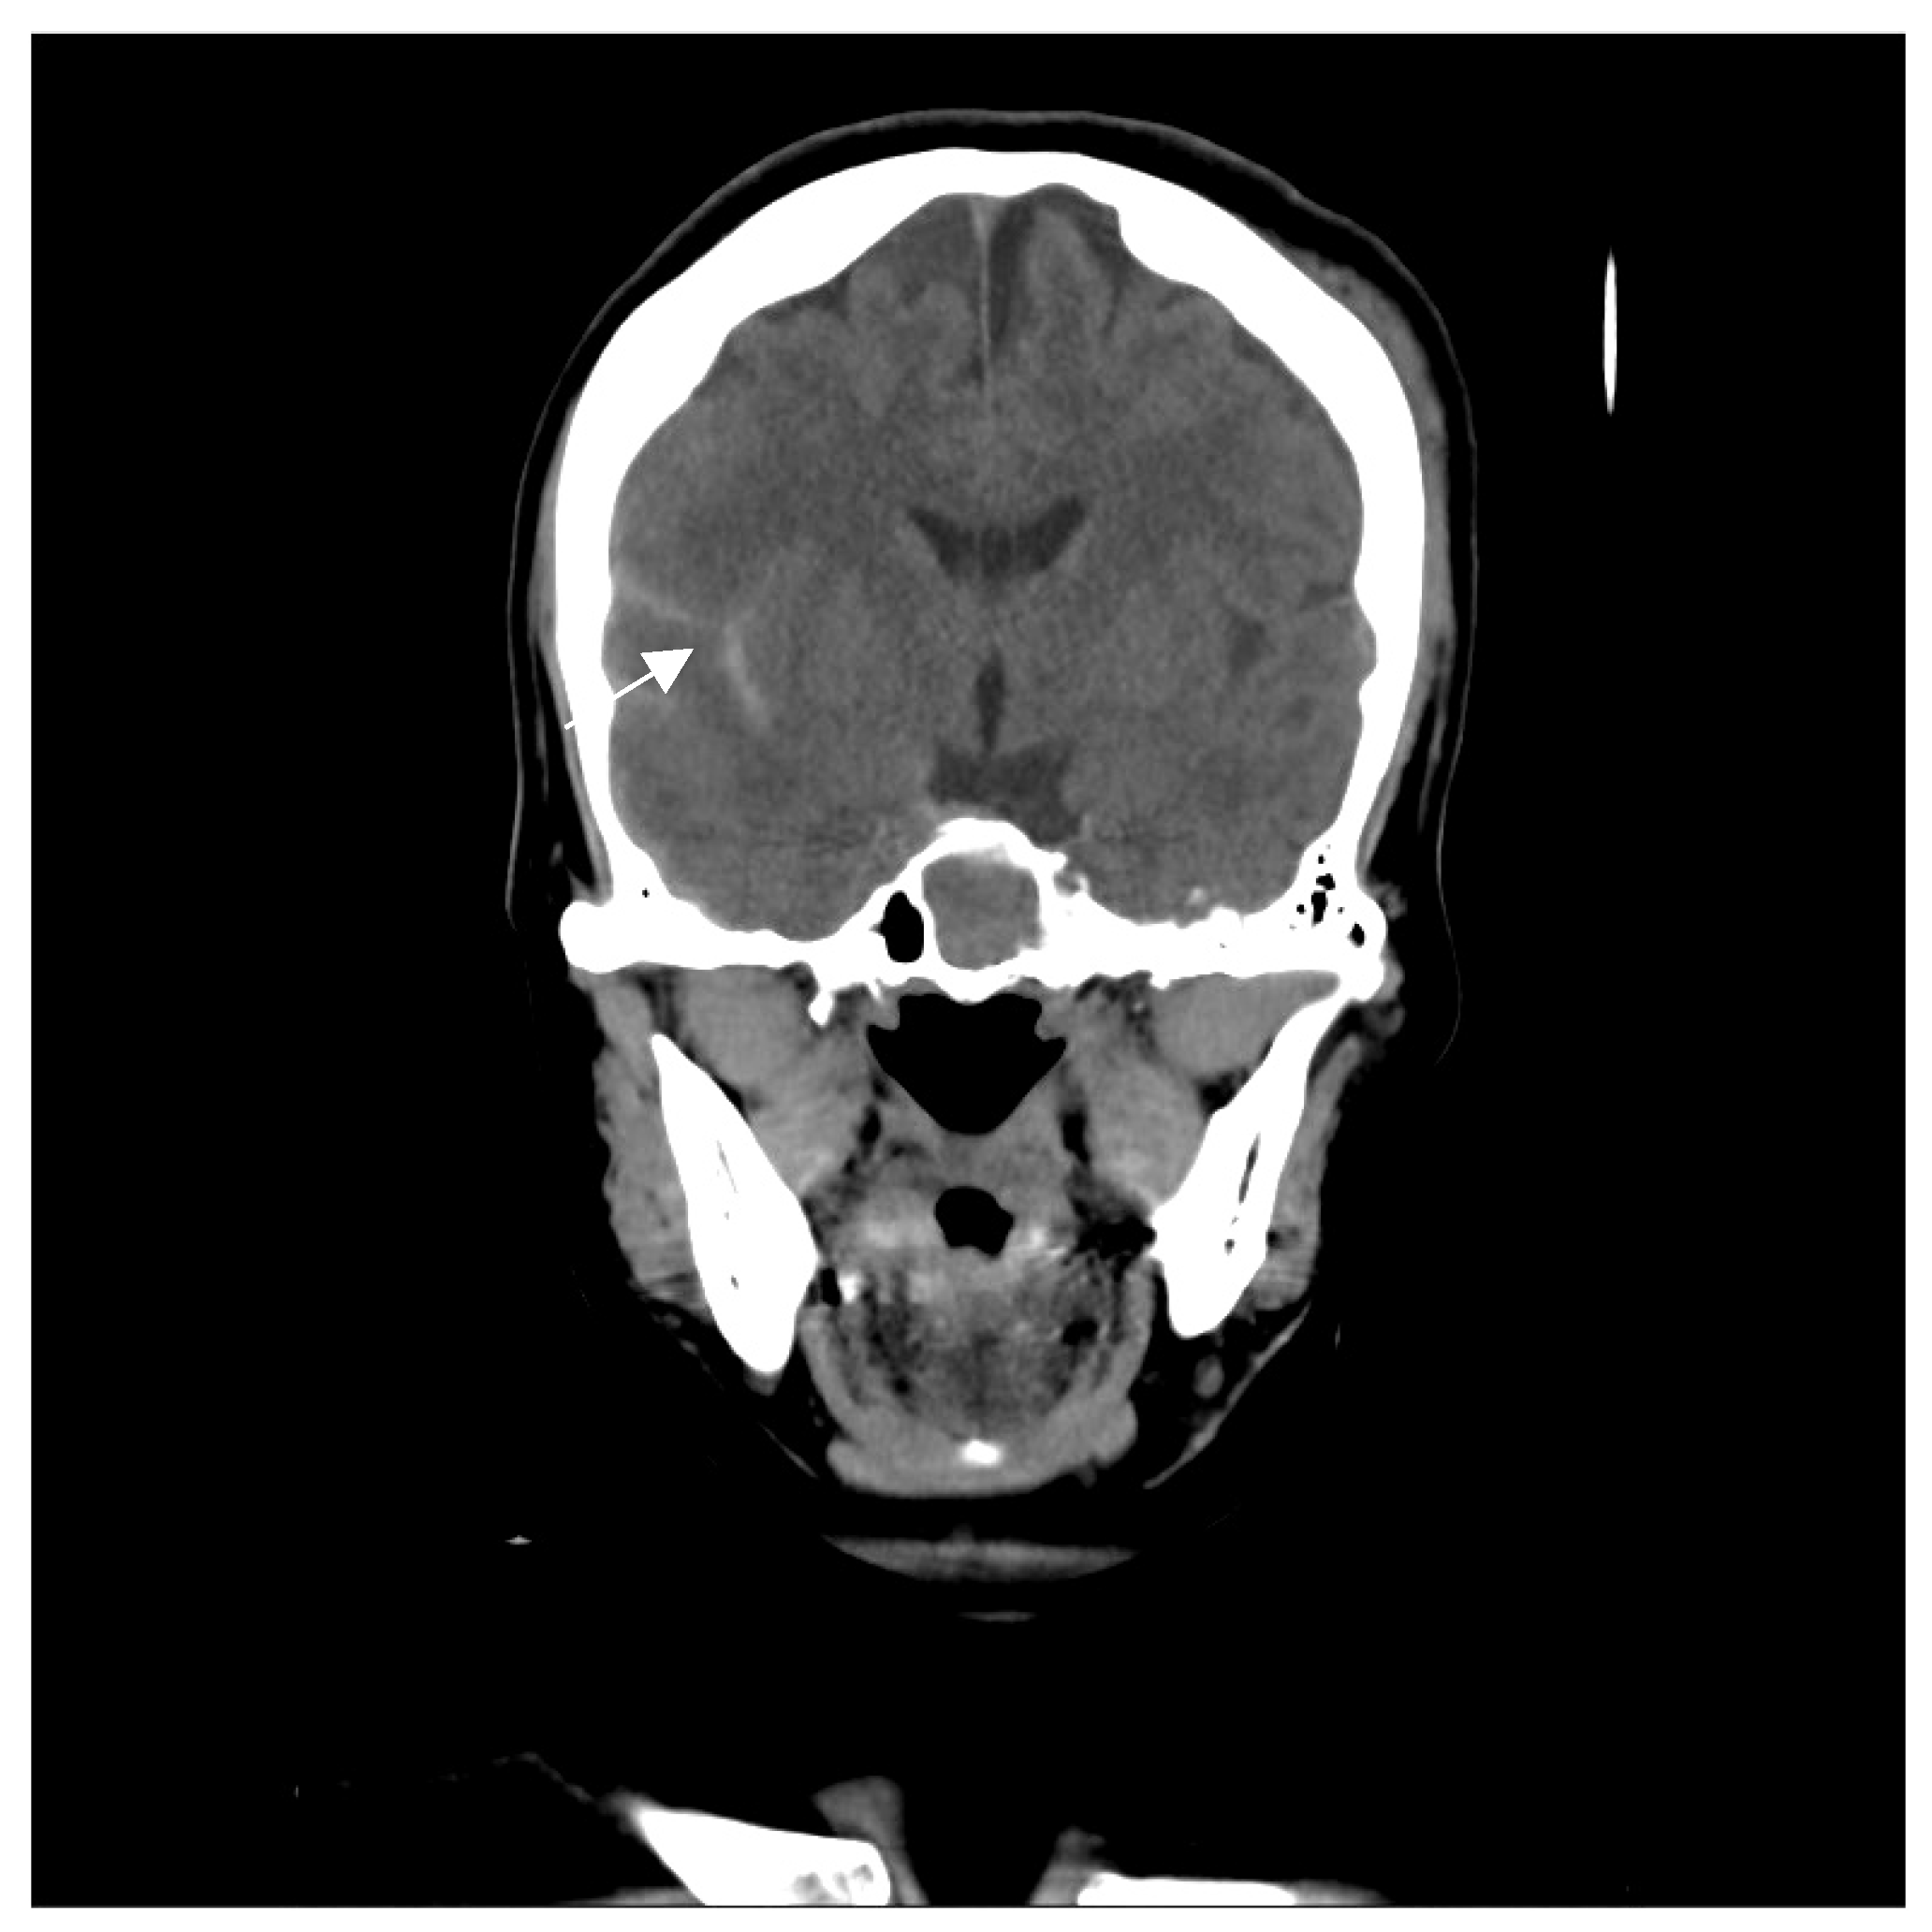

A 46-year-old woman with medically controlled hyperthyroidism was a victim of a motor vehicle accident on the road. The accident led to poor consciousness with Glasgow Coma Scale (GCS) level at E4V1M4, nasal bleeding, and left otorrhea in the patient. A brain computed tomography (CT) scan (Figure 1) showed a small subdural hematoma over the right temporal lobe, right Sylvian subarachnoid hemorrhage, and a right sellar floor fracture with sphenoid sinus hematoma upon arrival at the emergency room. The patient underwent right intracranial pressure monitor insertion for further monitoring and intensive care. Fortunately, the severity of traumatic brain injury did not progress. She gradually regained consciousness 3 days post-trauma. However, she complained of a progressive right eye floater and flash 4 weeks later, so she visited an ophthalmologist for further evaluation. Initial examination revealed right eye proptosis and conjunctival vessels engorgement, without chemosis, or tinnitus in the right ear. (Figure 2a) Rapidly progressive severe right eye exophthalmos, audible bruits, and chemosis (Figure 2b) developed within several days, highly suggesting right carotid cavernous fistula. The visual acuity and intraocular pressure data before treatment and one month post-treatment of the CCF are listed in Table 1. In addition, she became unconscious (GCS E3V2M5) and had left limb hemiplegia. A brain magnetic resonance imaging (MRI) (Figure 3a) disclosed engorgement of the right SOV and swelling of right orbital cavity (the MRI protocol we used is listed below in Table 2). In addition, high T2-weighted imaging signal changes were observed in the right corpus striatum (Figure 3b), right insular lobe, right inferior frontal lobe, right medial temporal lobe, midbrain, and pons (Figure 3c), which indicate perifocal brain edema.

Figure 1. The figure reveals a small subdural hematoma over the right temporal lobe (arrow), sylvian subarachnoid hemorrhage, and right sellar floor fracture with sphenoid sinus hematoma.